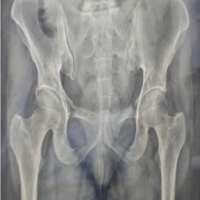

Materials and Methods: This is a retrospective study of 100 hips diagnosed with osteonecrosis/osteoarthritis of the femoral head that underwent THA at a tertiary care center before and after the COVID-19 pandemic between February 2014 and February 2024.

Osteonecrosis of the femoral head (ONFH) is a crippling hip joint disease primarily affecting young people [1]. The genesis, natural history, and epidemiology of ONFH remain largely unknown. ONFH is associated with a wide range of conditions and drugs. The emergence and resurgence of coronavirus disease 2019 (COVID-19) infection, which is still prevalent globally in low-grade form, is one such condition that has occurred recently. While COVID-19 infection and avascular necrosis (AVN) are prevalent, little research has been published on their association. AVN or osteonecrosis has been observed in several joints, including the knees, shoulders, and spine. However, the hip joint is the most commonly affected [2-6]. Although many issues with COVID-19 remain unanswered, numerous research and reports have indicated a substantial prothrombotic condition on both a micro and macrovascular level in patients with this infection. There is limited evidence that COVID-19 can cause AVN. The most frequent cause of ONFH is the judicial use of corticosteroids, which were once again extensively used during the pandemic to treat COVID-19 infection because they were a life-saving medication. According to new research, COVID-19 has a deleterious effect on multiple body systems as part of “long COVID-19.” The phrase “long COVID-19” refers to the long-term consequences of COVID-19 infection that linger for several weeks or months following the patient’s recovery. In addition, it was described by the National Institute for Health and Care Excellence as symptoms that persisted for longer than 12 weeks [7-9]. ONFH risk increased in tandem with the COVID-19 infection. It is impossible to ignore the connection between COVID-19 infection and ONFH given the incomplete understanding of its sequelae. In light of this, research on the etiopathogenesis of ONFH in the population of south India is lacking, especially with regard to its connection to COVID-19 infection. Treatment options for hip osteonecrosis are many in number, ranging from joint preservation measures and non-operative care to total hip replacement (THR). When an early diagnosis is made before the lesion has grown too large or there is radiographic evidence of femoral head collapse, non-operative or joint-conserving treatment may enhance the results. Primary THR is frequently the only effective therapy option available because many individuals present after the illness has progressed, especially for Stage 3 and 4 of Ficat and Arlet classification for osteonecrosis femoral head [10-12]. As a result, the recent increase in THR caused by ONFH piqued our interest in conducting this study.

With regards to the multiple diagnoses requiring THA, we have realized that it was primary osteoarthritis the maximum before the pandemic, whereas post-pandemic almost 80% were diagnosed to have femoral head AVN (FHAVN) (Table 4 and Fig. 3).

By which we have realized that post-pandemic FHAVN patients present to the hospital at late stages, much faster than before. On an attempt to study the association of corticosteroid intake with post-pandemic group specifically, we found that 12 patients who were managed by isolation and treatment at home, neither knew about medications nor did they have any substantiating documents at the time of the surgery. Even the two patients who were treated at the hospital apparently did not have any medical documents. Therefore, we could not analyze this association in any amount. Among 24 FHAVN patients in post-pandemic group, only five patients had a history of alcohol consumption and smoking, out of whom only two were tested positive for COVID-19 infection. Various instances were met during the investigation, and some examples have been illustrated here to offer an understanding of what and why we were inquisitive to perform this research (Fig. 6-8).

Our research focuses on long-term COVID-related orthopedic problems, specifically ONFH. At our set-up, FHAVN as a diagnosis for THA has increased dramatically to 80% post-pandemic (roughly 6 folds more), from 12.86% pre-pandemic. We discovered that the age range of people presenting with late-stage FHAVN had shifted from 46-60 years pre-pandemic to 31-45 years post-pandemic. Between the two groups, there is an increase in patients under the age of 30 undergoing THA. Both before and after the pandemic, the 31–45 age group continues to contribute the most to FHAVN resulting to THR, which validates with another study done among north-Indian population [16]. Contrary to our study, Okewunmi et al. concluded that there is an increase in THA due to FHAVN in older population in USA [20]. In addition, where males were the more likely to present with this condition, there has been a surge in the number of females having THR for the same diagnosis. Males continue to be the most typically affected by FHAVN, both before and after the pandemic. Following the pandemic, the number of bilateral FHAVN requiring THA increased significantly in our study center. We found that 58.33% of FHAVN patients tested positive for COVID-19, with the majority receiving medical care outside of the hospital. The average duration of FHAVN presentation necessitating THR has decreased significantly to 6.5 months, which is almost 6-fold faster. Although smoking and alcohol intake are strongly associated with FHAVN, only handful of the post-pandemic population had such a history [21]. We tried to analyze the usage of corticosteroid, the well-known risk factor for FHAVN, but there were no documentations of the same to investigate [22,23]. It was only recorded if patients were anytime during the pandemic were tested positive for COVID-19 infection or not. Suggested by different authors the COVID-19 pandemic could be a multi-factorial cause of FHAVN, increasing the burden of THR. Dhanasekararaja et al. [24] studied 22 patients who developed femoral head osteonecrosis after receiving corticosteroids to treat COVID-19. According to Agarwala et al., osteonecrosis in COVID-19 occurred even with a lower dose of corticosteroid treatment [25]. Sulewski et al. concluded that COVID-19 infection alone may serve as a risk factor for femoral head osteonecrosis [5]. ONFH has the potential to be the most bothersome “long-COVID-19” not just for orthopedic surgeons but also for the general public, especially when in our setup it is the farmers (belonging to low socioeconomic status) who present the highest for THA due FHAVN [26,27].